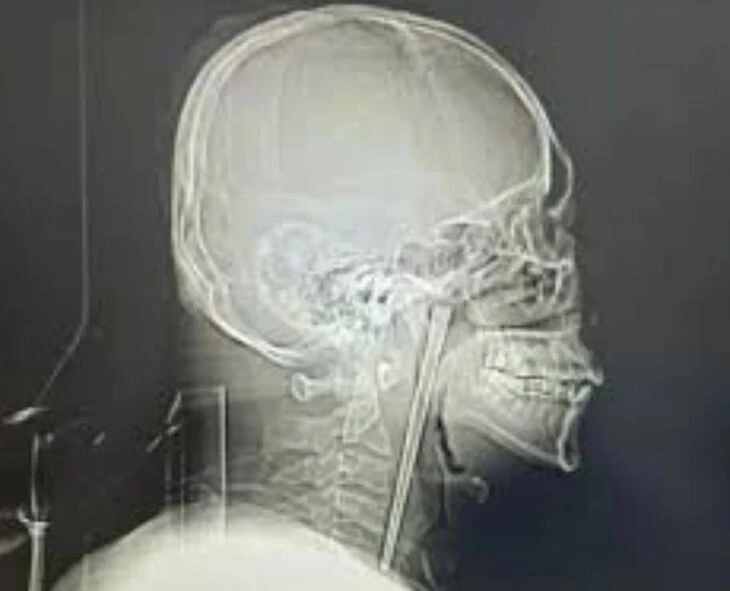

கழுத்தில் 12 செமீ குச்சியுடன் 8 ஆண்டுகள் வாழ்ந்தவர்!

சீனாவில் கழுத்து வலி என வந்தவருக்கு ஸ்கேன் எடுத்து பார்த்த போது, தொண்டையில் 12 செமீ நீளமுள்ள சாப்ஸ்டிக் இருந்ததை கண்டு டாக்டர்கள் அதிர்ந்துள்ளனர். ஆனால், அந்த நோயாளி எந்த சலனமும் இன்றி, அது 8 ஆண்டுகளாக தொண்டையில் இருப்பதாக கூறியுள்ளார். மதுபோதையில் நூடுல்ஸ் என நினைத்து சாப்ஸ்டிக்கை விழுங்கியவர், Operation-க்கு பயந்து அப்படியே விட்டுவிட்டாராம். தற்போது வலி தாங்காமல் ஹாஸ்பிடலுக்கு வந்துள்ளார்.